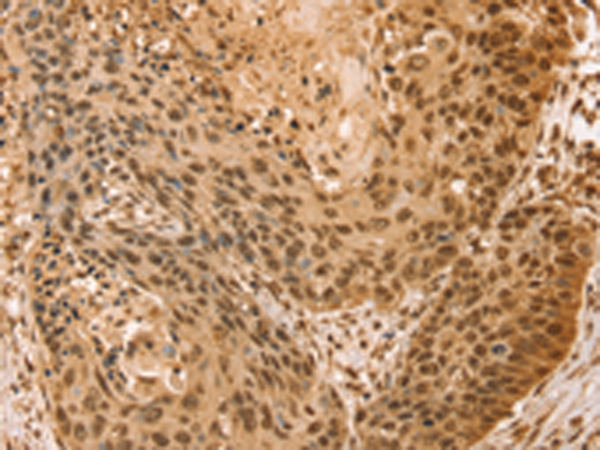

分类: 科研抗体货号: P01830别名: Mvp1应用: WB,IHC反应种属: Human, Mouse

分类: 科研抗体货号: P01824别名: SNO; SnoA; SnoI; SnoN应用: WB,IHC反应种属: Human, Mouse

分类: 科研抗体货号: P01821别名: SNAP-23; SNAP23A; SNAP23B; HsT17016应用: WB,IHC反应种属: Human, Mouse, Rat

分类: 科研抗体货号: P01882别名: TCFEB; BHLHE35; ALPHATFEB应用: WB反应种属: Human, Mouse

分类: 科研抗体货号: P01906别名: CC3; TIP30; SDR44U1应用: WB反应种属: Human, Mouse

分类: 科研抗体货号: P01874别名: EBI; TBL1; SMAP55应用: WB,IHC反应种属: Human, Mouse

分类: 科研抗体货号: P01903别名: RNF9; HERF1; RFB30应用: WB,IHC反应种属: Human

分类: 科研抗体货号: P01868别名: TAF2I; PRO2134; TAFII28; MGC:15243应用: WB,IHC反应种属: Human, Mouse, Rat

分类: 科研抗体货号: P01898别名: AFP; RNF95; ZNF173应用: WB,IHC反应种属: Human, Mouse, Rat

分类: 科研抗体货号: P01859别名: slp5应用: IHC反应种属: Human, Mouse, Rat